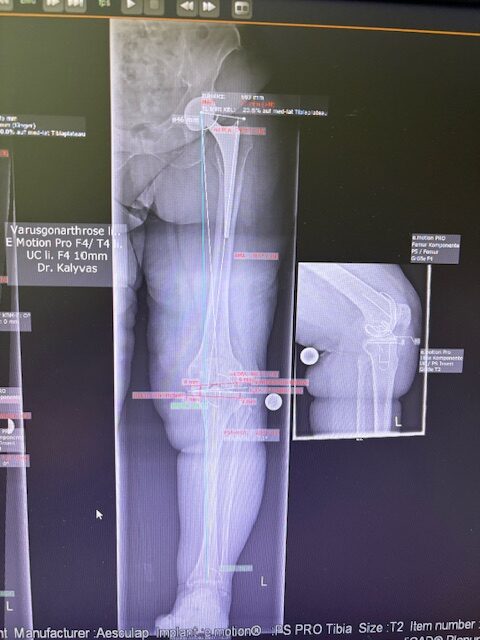

Ο προεγχειρητικός ψηφιακός σχεδιασμός

Πραγματοποιήθηκε σε ειδική ακτινογραφία ολόκληρων των δύο κάτω άκρων. Σε αυτό το ψηφιακό μοντέλο σχεδιάστηκε με ακρίβεια το είδος, το μέγεθος και η ακριβής θέση των προθέσεων, με βάση τα ανατομικά χαρακτηριστικά της ασθενούς.

Ο ψηφιακός σχεδιασμός επιτρέπει απόλυτη εφαρμογή των μοσχευμάτων, ελαχιστοποιώντας τα περιθώρια απόκλισης και εξασφαλίζοντας άριστη ευθυγράμμιση και κινηματική ισορροπία του γόνατος.

Τα εμφυτεύματα που χρησιμοποιήθηκαν στο γόνατο της ασθενούς είναι της Aesculap: E-Motion Pro, μηριαίο μέγεθος 4, κνημιαίο μέγεθος 4, με ενθέμα (inlay) 10mm.